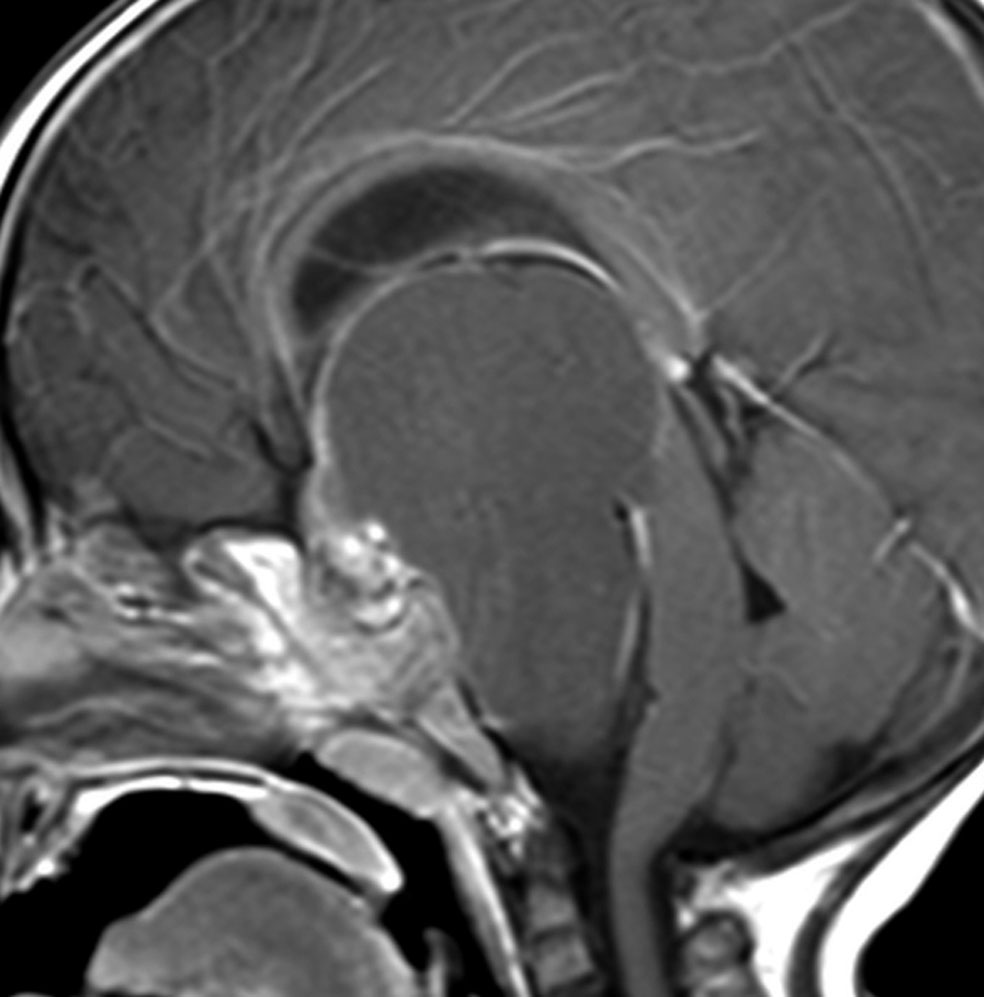

この子の症状は頭痛だけ。両親はなぜ気づかなかったのかと疑問を持ちますが,巨大になるまで症状が出ないこともあるのです。左のCTで腫瘍の周囲にバラバラと白い点状の石灰化があるので診断できます。左の視床下部から発生したクラニオでした。開頭手術しますが超高難易度です,怖いです (┯_┯) 複数回開頭手術になりましたが結果的に全摘出できています (by Dr 山本哲哉)。

ちょっと大きな頭蓋咽頭腫です

嚢胞(液体が入っている袋)の部分と,腫瘍細胞が固まっている実質部分が入り交じっています。このくらいの大きさになってしまうと,下垂体機能を残すことはとても難しくなります。視神経が圧迫されて視力低下と視野障害を生じます。第3脳室が腫瘍で閉塞していて水頭症になっていますから知能の活動が低下します。

腫瘍を摘出するのに危ないのは,脳の血管の損傷です。左では白く,右では黒く線状に移っているのが太い脳動脈です。これら以外にもたくさんの細い重要な動脈が絡んでいます。

幸いこの患者さんの腫瘍は摘出できて患者さんは元気になりました。でもこのくらいのサイズになると手術がいつもうまくいくとは限りませんし重大な障害が残ることもあります。